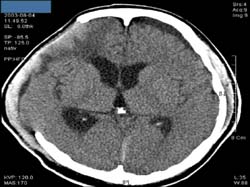

<³úÃâÇ÷ÀÇ

CT>